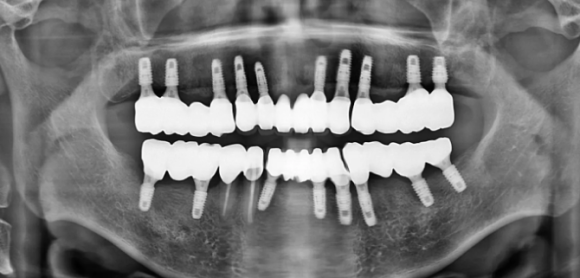

치료 전

치료 후 전악 임플란트

임플란트 시술 후에도 1개월, 6개월 단위의 정기 점검을 통해 작은 문제도 놓치지 않으며, 필요할 경우 추가적인 관리 계획을 세워 환자분들이 오래도록 건강한 치아를 유지할 수 있도록 돕습니다.